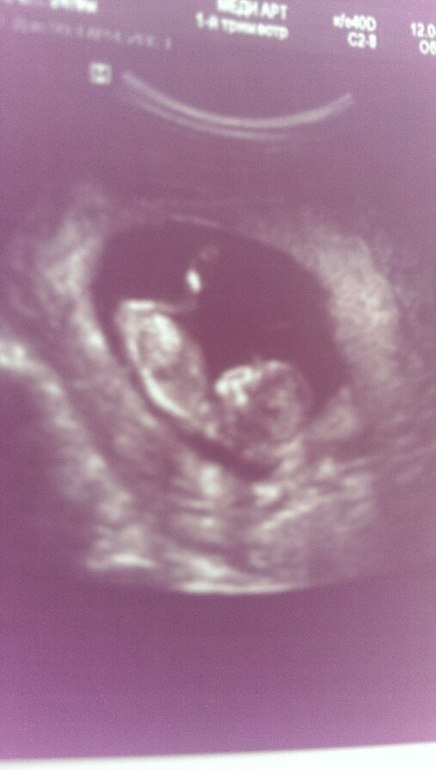

Ну и бонус - вчера ходили на 1 скрининг, сдали кровь и сделали узи. Результаты крови ждем в субботу, а вот наш УЗИ:

Все у нас хорошо! Но насчет пола врач не стала делать никаких предположений)